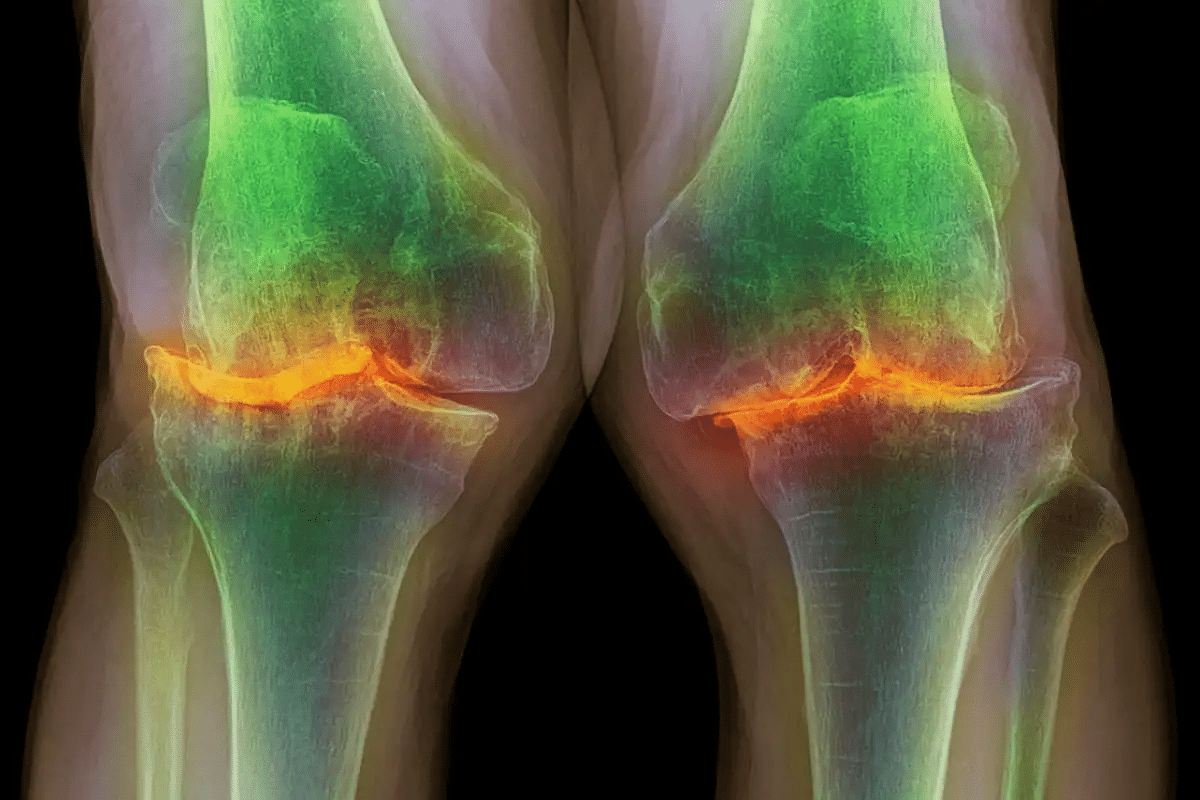

Knee Joints: The Most Vulnerable Target

The knee joints are often hit hard by osteoarthritis. Their complex design and weight-bearing role make them vulnerable.

Knowing which joints are most affected is key to good self-care. By focusing on the most at-risk areas, we can take steps to manage the condition and prevent more damage.